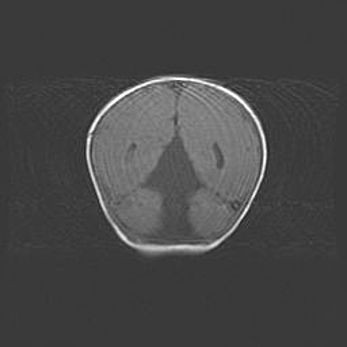

Неполная лизэнцефалия (пахигирия). Открытая гидроцефалия.

Возраст: 17 дней

Вес: 3110 г

Пол: мужской

Окружность головы: 33,5 см

Срок гестации: 35-36 недель

Лизэнцефалия—недоразвитие корковой пластинки и мозговых извилин в результате нарушения миграции нейронов коры. Поверхность мозговых полушарий гладкая. Микроскопически выявляется отсутствие нормальных слоев коры и скопление групп нейронов в подкорковом белом веществе.

Пахигирия—уменьшение числа вторичных извилин. В пораженном полушарии нервные клетки образуют толстый недифференцированный слой с неправильно расположенными нервными волокнами и группами гетеротопных клеток. Нервные клетки незрелые. Белое вещество истончено. При этом нередко аномально развит корково-спинномозговой путь.